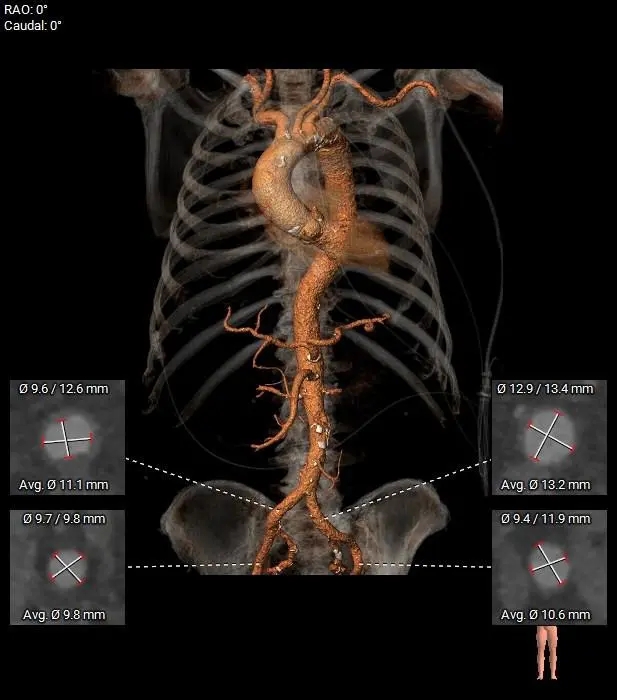

双入路、多选择|石河子大学第一附属医院贺贵宝、薛亚军教授团队应用ScienCrown的单中心经验

近期,石河子大学第一附属医院贺贵宝、薛亚军教授团队凭借丰富的临床经验,成功应用ScienCrown自膨胀短瓣,完成了多例高难度经导管主动脉瓣置换术(TAVR)。这些复杂病例涵盖了重度主动脉瓣狭窄、横位心、单纯主动脉瓣反流等多种疑难情况。手术团队根据每例患者的具体解剖特点与病情需求,充分发挥了ScienCrown瓣膜“双入路”(经股动脉及经心尖)的独特优势,为患者“量身定制”最优手术方案。所有病例均通过单一瓣膜植入获得成功,未发生一例“瓣中瓣”事件。

贺贵宝教授指出,患者的解剖结构与临床需求存在显著个体差异,一款支持双入路的瓣膜能够为复杂病例提供更为灵活和全面的治疗选择。他进一步介绍,ScienCrown瓣膜的直筒型瓣架设计,有助于在主动脉根部实现多阶段稳定锚定,因此在瓣膜尺寸选择上无需过度追求oversize;同时,其“全释放/全回收”的功能特性,允许术者在最终释放前更充分地评估瓣膜的定位与稳定性,从而确保了瓣膜的精准植入,有效提升了手术安全性与疗效。

在近期的经导管主动脉瓣置换术(TAVR)实践中,石河子大学第一附属医院贺贵宝、薛亚军教授团队再次展现了其卓越的临床决策能力与手术技艺。他们凭借深厚的临床经验积累,并紧密结合每一位患者的个体化解剖特点,精准制定手术策略,充分发挥了ScienCrown瓣膜独特的“双入路”设计优势,成功攻克了多例高难度TAVR病例。贺贵宝教授强调,临床实践中患者的解剖结构千差万别,针对不同患者的具体情况选择最适宜的手术方式,是医者仁心与专业素养的体现。一款能够同时兼容经股动脉和经心尖两种入路的瓣膜,为术者提供了更为灵活的选择,有助于为患者量身打造并实施最合适的个体化诊疗方案,从而更好地服务于患者,保障手术疗效与安全。

国产创新自膨短瓣Sciencrown在PAR中的核心优化:

短瓣架设计:短瓣架设计,更短的释放行程,快速锚定贴靠

直筒型设计:直筒形态,多节段参与锚定,提供更平衡的径向支撑力

双层裙边设计:PET内外双裙边设计,提供更大摩擦力,保障瓣膜稳定

全释放/全回收设计:100%全展开,瓣膜整体参与锚定,评估更精准更安心

预弯型设计:瓣膜装载后胶囊段自带30°弯型,瓣膜释放过程更同轴

管榫挂钩设计:12个挂钩设计,逐一释放,分散脱钩张力,实现零张力脱钩